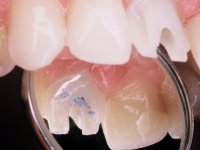

After the impression of the implant using a double-mix technique with double viscosity and the collection of shape and color information by the ceramist, we proceed with the work. In the model, a syn octa was placed over the implant, and a screw was placed on it to assess its emergence in relation to the incisal edge. Then, an adequate emergence profile in the artificial gingiva was prepared. A abutment with characteristics suitable for overbite and simultaneously capable of receiving a veneer was waxed on top of this scenario. This waxing gave rise to the manual milling of a very personalized abutment. An infrastructure in Zr was also made for the veneer with a very great adaptation to the abutment. On this infrastructure ceramics were placed. Ceramic fluorescence sought to compensate for the lack of fluorescence that Zr had and obviously further customize the aesthetics. The adhesive bridge was removed and the definitive work was placed. The syn octa was initially tightened with 35 N to the implant and then the Zr abutment was tightened over the syn octa with 15 N. The access hole was plugged and then the veneer was cemented with resin-reinforced glass ionomer. After 15 years, the patient returned to the consultation with tooth mobility. Fortunately, nowadays we have the possibility of having dynamic tightening wrenches that allow tightening screws with greater inclinations. An access cavity was made without damaging the incisal edge of the veneer. Tightening was done with a dynamic wrench with 15 N torque. The hole was covered with Teflon and filled with composite resin. This solution allowed the problem to be solved in a simple and economical way.